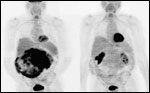

Importantly, drug-related toxicity was not significant in the patients enrolled in this trial; indeed, any toxicity was quite manageable, as evidenced by the fact that 82% of patients remained on study with a median follow- up > 9 months. In addition, the study established that abrogation of tumor glycolytic activity as demonstrated by 18-fluorodeoxyglucose positron-emission tomography (PET) was an early and accurate predictor of response in these PET-avid tumors (Figure 2).[30] This type of PET response was seen in many cases even in the absence of typical regression on traditional cross-sectional imaging and was noted early in drug treatment.

FIGURE 2

Pre- and Posttreatment PET Scans